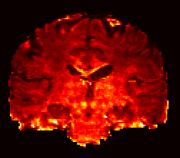

Figure 6 shows the intracellular and CSF volume fractions estimated using NODDI and NODDI-SH, respectively. The maps obtained with the two techniques are very similar. NODDI-SH intracellular volume fraction appears to be slightly more contrasted with respect to NODDI, in particular in single fiber areas such as the corpus callosum and the corticospinal tract. NODDI-SH CSF map presents more voxels with higher partial volume of CSF near the cortex, but in general, the agreement between the two maps is extremely high. For both models, CSF fraction maps present low, but non-zero, values in the white matter. Although the presence of free water between the axons is not likely, these values could be explained by an intrinsic error of the three compartment model used by both techniques.

Figure 7 shows the MSE calculated between the normalized diffusion signal and the estimated diffusion signal of NODDI and NODDI-SH. It is worth to mention that in this picture we use a very narrow range of values in order to emphasize the contrast and that both techniques were able to estimate the diffusion signal accurately. NODDI MSE appears to be higher in white matter, and in particular in single fiber areas, with respect to gray matter or CSF where it is close to zero. NODDI-SH MSE presents a more uniform pattern in the white matter, gray matter, and CSF. The highest MSE values for NODDI-SH were found in the corpus callosum and in the basal nuclei.